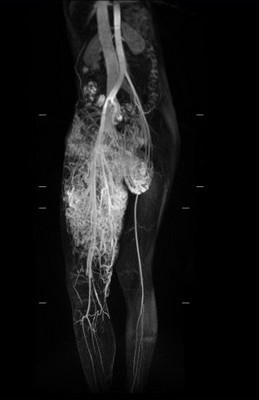

右圖:小班克右腿的動脈與靜脈是沒有經過微血管就直接相接的「動靜脈畸形」,兩腿間動靜脈血管畸形腫瘤已成為拳頭大小

「小班克右腿的動脈與靜脈是沒有經過微血管就直接相接的『動靜脈畸形』,這是最不容易處理的狀況。」主治醫師整形暨重建外科主任李俊達表示,若要手術移除小班克的動靜脈血管畸形及微血管畸形並不容易,因為她大腿深部的動脈與靜脈連接在一起,從下腹部延伸至鼠蹊部、右大腿,加上包覆大腿皮膚表層的微血管畸形面積很大,若使用雷射方式移除,得進行十次以上的雷射手術,還可能引起大出血;另一種治療方式則是使用栓塞手術,但可能會造成皮膚潰爛或引起併發症,若要全部移除是較為困難。經過醫療團隊仔細的評估,治療方式優先以移除影響小班克生活最大的動靜脈畸形瘤為主,李俊達主任說,先由臺大醫院影像醫學部腹部影像診斷科梁博欽主任透過血管栓塞手術減少腫瘤的血液供給量,待動靜脈血管畸形瘤因為供血量減少,開始發黑萎縮後,接著由李俊達主任、整形外科團隊及臺大醫院整形外科主任戴浩志聯手移除腫瘤,並使用超音波刀邊切除邊將血管阻塞,不僅對正常的皮膚組織傷害較小,也能降低出血量。手術順利於三小時內切除了直徑約十公分,總重兩百七十公克的腫瘤。